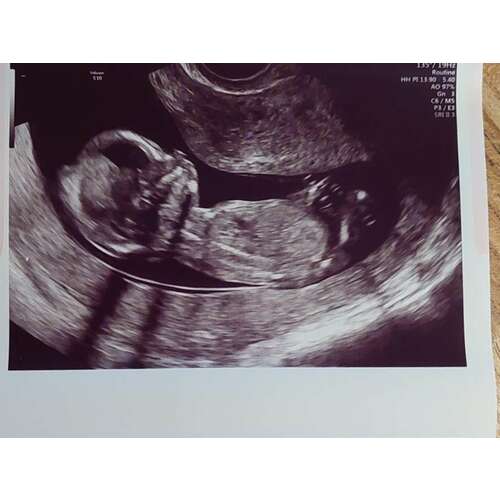

Dit is de bevestigde meisjes nub 🥰

Zo benieuwd of hier iets op te zien is bij 13.3? Zelf kan ik er niets van maken. Hopelijk @nubster wel🙂.

Ik ben zo benieuwd!! Kun je de nub zien?

Zover ik kan zien denk ik 💗